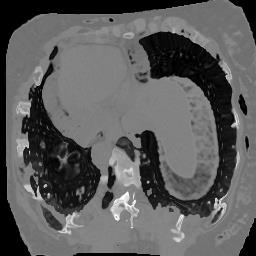

In clinical practice, well-aligned multi-modal images, such as Magnetic Resonance (MR) and Computed Tomography (CT), together can provide complementary information for image-guided therapies. Multi-modal image registration is essential for the accurate alignment of these multi-modal images. However, it remains a very challenging task due to complicated and unknown spatial correspondence between different modalities. In this paper, we propose a novel translation-based unsupervised deformable image registration approach to convert the multi-modal registration problem to a mono-modal one. Specifically, our approach incorporates a discriminator-free translation network to facilitate the training of the registration network and a patchwise contrastive loss to encourage the translation network to preserve object shapes. Furthermore, we propose to replace an adversarial loss, that is widely used in previous multi-modal image registration methods, with a pixel loss in order to integrate the output of translation into the target modality. This leads to an unsupervised method requiring no ground-truth deformation or pairs of aligned images for training. We evaluate four variants of our approach on the public Learn2Reg 2021 datasets \cite{hering2021learn2reg}. The experimental results demonstrate that the proposed architecture achieves state-of-the-art performance. Our code is available at https://github.com/heyblackC/DFMIR.